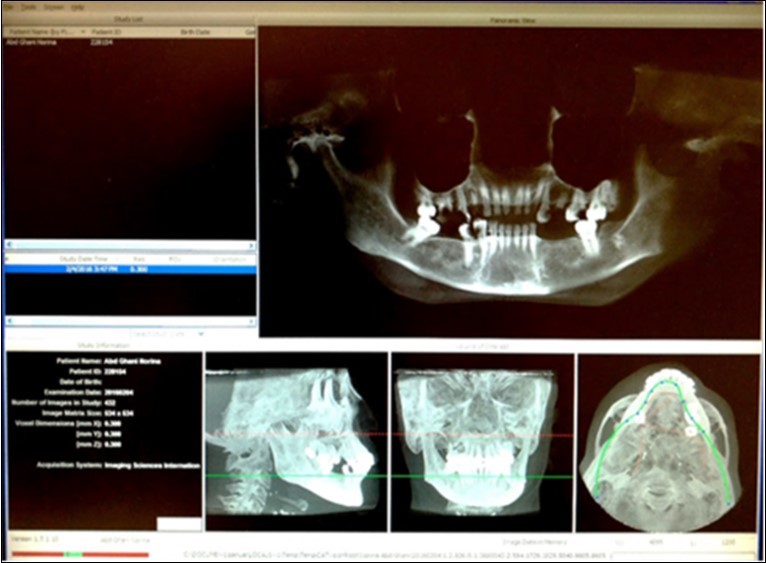

The maxillofacial CBCT examination was performed using i-CAT cone beam computed tomography (Imaging Sciences International, Hatfield, PA, USA) with tomography specifications of Tube Potential (Kv) 120, Current (mA) 5, Voxel Size (mm) 0.3 and scan time (s) 20-40 (Figure 1). Image analysis was performed using the i-CAT Vision Software, employing the multiplanar reconstruction (MPR) window in which axial, coronal and sagittal planes were visualized in 0.3mm intervals.